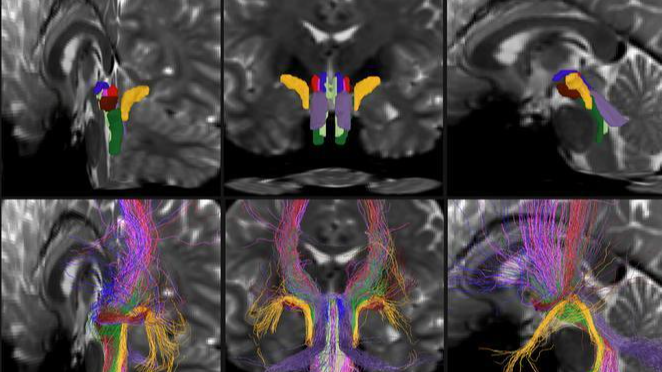

該軟件名為“腦幹束工具”(BSBT),基於擴散磁共振成像數據,利用卷積神經網絡自動識別並分割出腦幹中8個不同的白質神經束。此前,由於腦幹區域結構複雜、易受生理運動及腦脊液幹擾,傳統成像技術難以對其神經束進行精細刻畫。

研究團隊首先利用人類連接組計劃的30例高分辨率影像數據對算法進行訓練,並通過屍檢解剖結果驗證其分割準確性。測試表明,BSBT在不同時間點對同一受試者的掃描結果中表現出高度一致性,且適用於多類影像數據集。